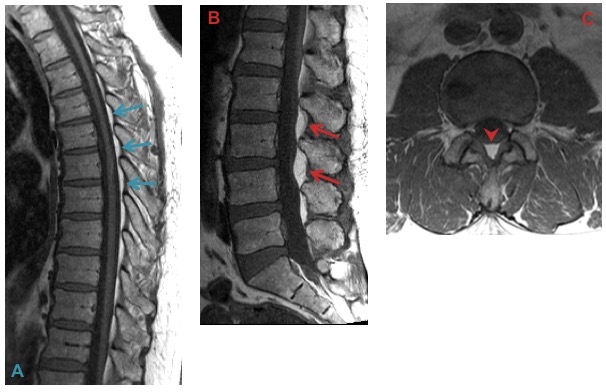

b) Sequestered discs: These discs have a different signal intensity from the parent disc and may show peripheral enhancement on CE-MRI.

Signal intensity of sequestered discs (A & B) is often different from the parent disc. Peripheral enhancement on CE-MRI (C) helps in identifying sequestration.